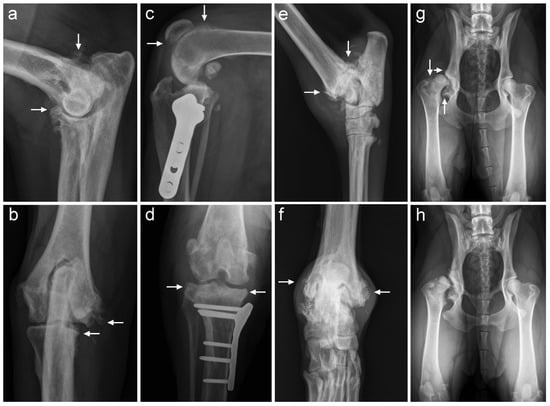

3.3.3. Radiographic Evaluation